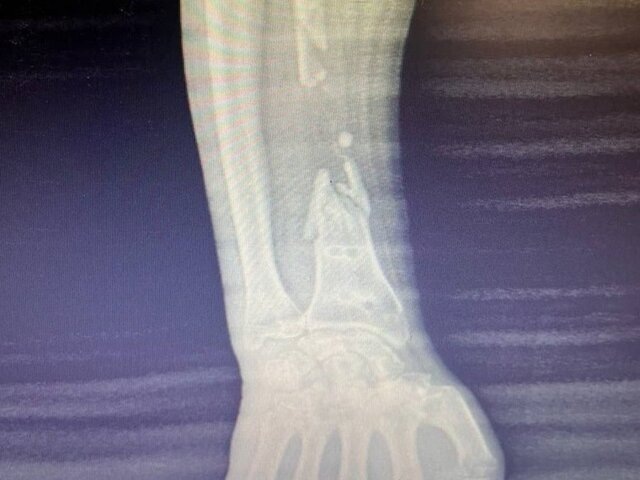

Специалисты Мытищинской больницы помогли 45-летнему пациенту с обширной открытой раной и многооскольчатым переломом лучевой кости правой руки. Об этом сообщили в пресс-службе . По словам хирурга-ортопеда-травматолога Амира Акмалходжаева, на первом этапе восстановления конечности врачи закрыли рану мужчине, а после ее заживления запланировали установку протеза. Хирург отметил, что пациент имел редкий дефект лучевой кости: ее суставные части были сохранены с двух сторон, а середина раздроблена на осколки. Сложная травма потребовала от врачей нестандартного подхода в решении ситуации. Благодаря скоординированной работе мультидисциплинарной бригады специалистов мужчине удалось оказать необходимую помощь. Изучив результаты компьютерной томографии обеих рук пациента до операции, они создали индивидуальную 3D-модель будущего протеза, а затем изготовили титановый стержень и силиконовую форму. Хирургическое вмешательство, продлившееся около двух часов прошло успешно. Спустя неделю мужчина смог

Хирург отметил, что пациент имел редкий дефект лучевой кости: ее суставные части были сохранены с двух сторон, а середина раздроблена на осколки. Сложная травма потребовала от врачей нестандартного подхода в решении ситуации.

Благодаря скоординированной работе мультидисциплинарной бригады специалистов мужчине удалось оказать необходимую помощь. Изучив результаты компьютерной томографии обеих рук пациента до операции, они создали индивидуальную 3D-модель будущего протеза, а затем изготовили титановый стержень и силиконовую форму.